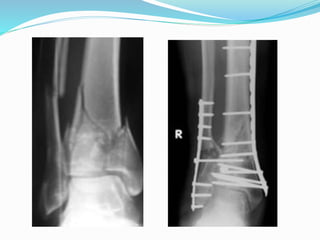

Types of surgical treatement

 1. ORIF, Open Reduction Internal ‘‘rigid’’ Fixation

 2 External Fixation with minimal osteosynthesis

 3 Closed Reduction Internal ‘‘biological’’ Fixation.

(MIPPO Technique)

 4. Intramedullary nailing

 5.Two stage protocol

TWO STAGE PROTOCAL

 All B3 and C type 0f

AO/OTA

 Ruedi & Allgower type 3

 1. Fix the # fibula(90%)

through postero lateral

approach to regain the

correct lengh of the tibia

and facilitate three

dimensional view of the

fracture

 2.External fixator-

a)Ankle Spanning -rigid

-articulated

b) Non spanning -

illizarov

-hydride

First step

Second stage

 After 10-14 days average(10

days)

 Remove the Ex Fix

 Through antero lateral

incision

 Articular reduction & fixation

with pre countered plate and

screws

 Additional antero medial

incision may require to fix

MM or large medial fragment

 Two incision required-

maintain not<6-7 cm

between two incision